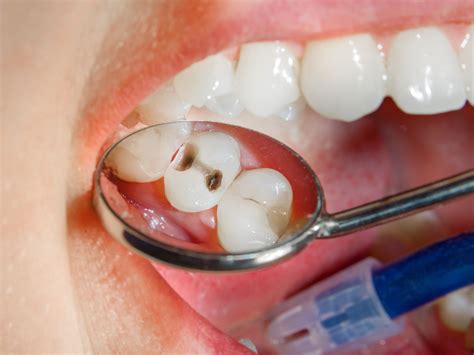

• Deep decay or cavities that reach the nerve chamber.

If this inflammation or infection is left untreated, it can cause severe pain, lead to an abscess, or result in the complete loss of the tooth. The primary goal of a root filling is to clean out the infected area and seal it, allowing the tooth to remain functional in your mouth.